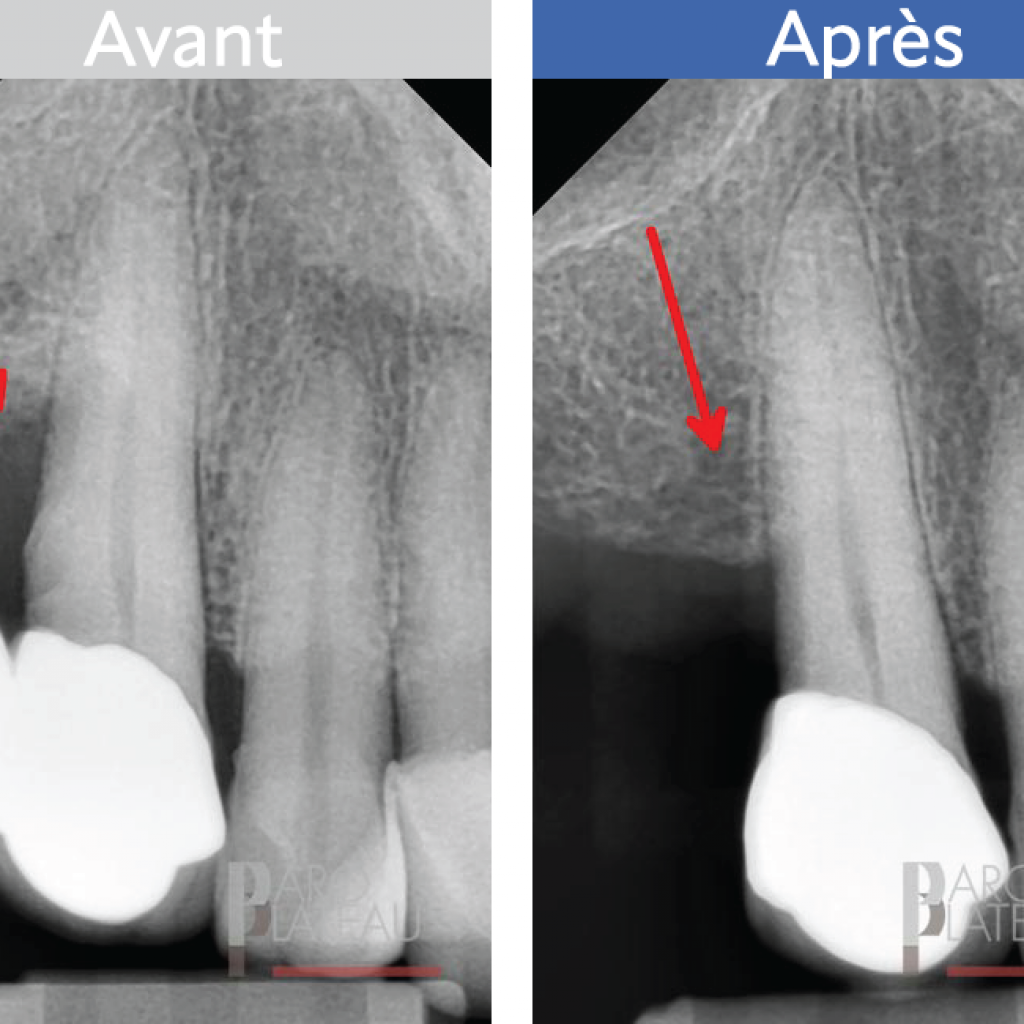

L’élongation coronaire

Cette procédure est nécessaire lorsqu’une carie profonde ou la fracture d’une paroi d’une dent se produisent. Il faudra alors dégager le pourtour de la dent afin de la rendre accessible à la restauration.

Avant

Après